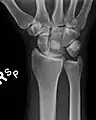

Dislocated lunate